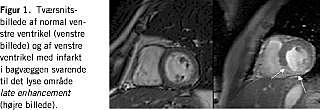

Med kontrastforstærket billeddannelse med gadolinium-diethylen-triamin-penta-acetat (DTPA) er det muligt at skelne mellem vitalt og ikkevitalt myokardievæv. Gadolinium er et paramagnetisk stof, som ved sin tilstedeværelse i vævet medfører signalforstærkning. Når gadolinium er hæftet til DTPA (Ga-DTPA), kan dette kompleks ikke passere den intakte cellemembran i normale myokardieceller. Ved iskæmisk skade og ved tilstedeværelse af fibrose ses derimod optagelse af Ga-DTPA i vævet og en karakteristisk langsom udvaskningskinetik, som gør det muligt, 15-20 min efter intravenøs injektion med Ga-DTPA, at se veldefineret signaløgning som lyse områder (late enhancement ) i billedet (Figur 1). Ved at kombinere optagelser med fremstilling af regional kontraktilitet og vævskarakteristik får man mulighed for at karakterisere områder med kontraktil dysfunktion som vitalt (viabelt) eller ikkevitalt. Dette har potentiel klinisk betydning for stillingtagen til revaskulariserende behandling hos patienter med hjertesvigt.